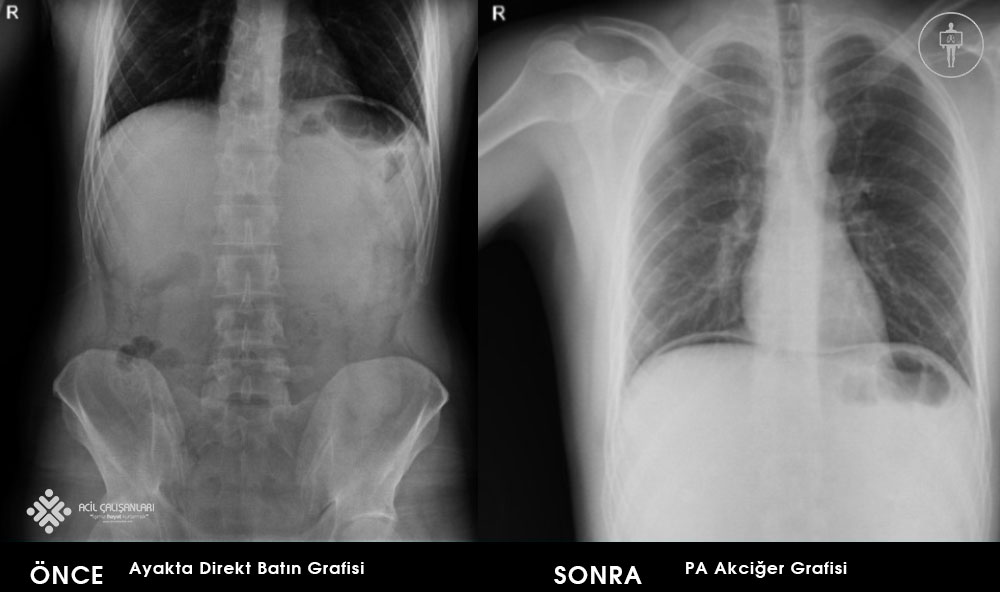

26 yaşında erkek hasta, ani başlayan karın ağrısı nedeni ile acil servise başvuruyor. Yeşil alanda değerlendirilen hastanın anamnezinde; karın ağrısının bugün başladığı ama 3 gündür dışkı yapamadığı, kronik hastalığı olmadığı ve ara sıra dispeptik şikayetleri olduğunu bu yüzden Gaviscon® şurup içtiğini öğreniliyor. Hasta değerlendirildiğinde, GKS: 15, nabız: 96 atım/dk ve düzenli, solunum sayısı: 18 soluk/dk, SpO2: %96, parmak ucu kan şekeri: 108 mg/dl ve kan basıncı: 150/60 mmHg olarak saptanıyor. Acil hekiminin muayesinde; solunum, kardiyak muayelerini normal, batın muayesinde sol üst kadranda hassasiyet saptıyor, defans ve rebound saptamıyor. Ayrıca bağırsak seslerii artmış ve rektal tuşe de rektumu boş olarak değerlendiriyor. Diğer sistem muayeneleri doğal olarak izleniyor. Acil hekimi öncelikle hastadan ayakta direkt batın ve PA akciğer grafisi istiyor. Bundan sonraki yaklaşımda aşamalarıyla doğru olan seçenek hangisidir?

Gastrointestinal kanal perforasyonu peptik ülser hastalığı, travma, iyatrojenik, yabancı cisim, apandisit, enflamasyon, tümör gibi nedenlerle ortaya çıkmakta ve erken tanı ve zamanında cerrahi müdahale ile mortalitesi ve morbitesi oldukça azalmaktadır. Gastrointestinal kanal perforasyonnları mortal seyrettiği için gözlem alıntında tutulmalı, oral stoplanmalı ve ana tedavi yöntemi cerrahi olduğu için hasta bir an önce genel cerrahiye danışılması gerekmektedir. Ayakta batın grafisi acillerde, akut karın ağrılarının değerlendirilmesinde ayakta batın grafisi sık olarak istenmektedir. Akut karın ağrısının tanısal incelemesinde akciğer ve karın grafilerinin yeri ile ilgili yapılan yayınlarda, grafilerin tanı konulmasındaki etkinliklerinin ve tedaviyi yönlendirmelerinin oldukça kısıtlı olduğu, akut karın ağrısı şikayeti ile acil servise başvuran her hastadan direkt grafi tetkiki istenilmesi halinde, tanıya yardımcı patolojik bulgu elde edilme oranı ortalama %10 olduğu gözlemlenmektedir. Bu yüzden acil cerrahi hastalıklar arasında en sık intestinal obstrüksiyon ve gastrointestinal perforasyon için karın grafilerinin tanısal etkinliği etkinliğe sahiptir. Bu yüzden klinik ve fizik muayene bulguları intestinal obstrüksiyon ve gastrointestinal perforasyon lehine değerlendirilen hastalarda direkt karın grafisi ilk tetkik olarak istenmelidir. Ancak, akut apandisit dâhil diğer akut karın patolojilerinde direkt karın grafilerinin kullanılması yetersiz tanısal etkinlik ve radyasyon riski açısından uygun gözükmemektedir.